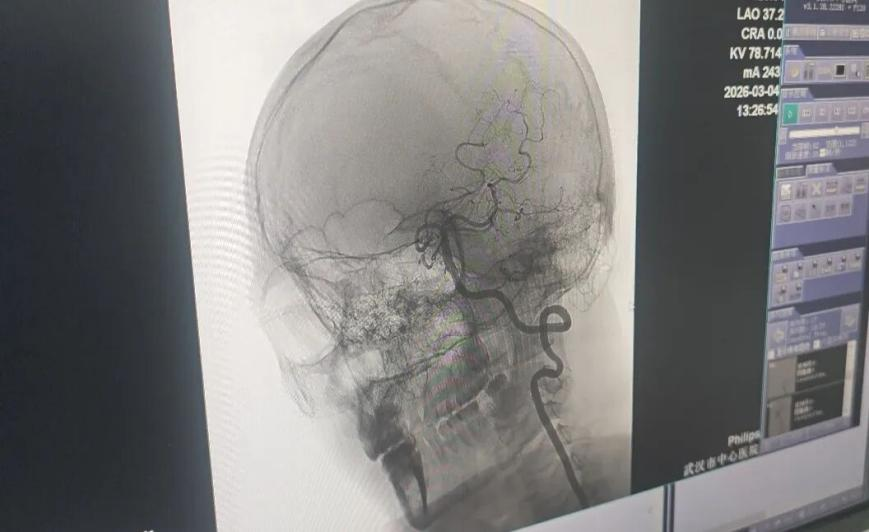

紧急送到医院后,医生给出了明确诊断:颈部不当强力按压,引发椎动脉血管夹层,最终诱发脑梗。①

医生疏通王先生堵塞的血管。长江日报记者李慧紫摄